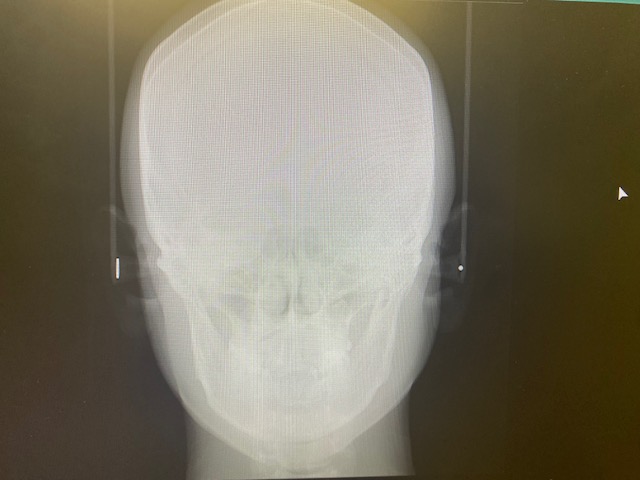

② レントゲン(正面セファロ・側面セファロ・パノラマ)

(👆 当院設置のCTスキャン画像)